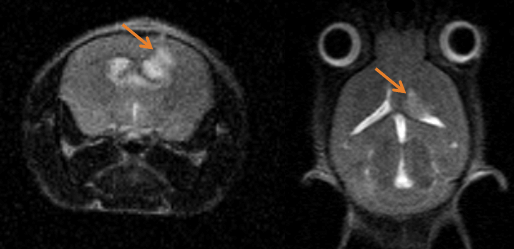

Epilepsy in the rat brain: T2- weighted images of a rat brain 48 hours after induction of epilepsy. Image Credit: Scintica Instrumentation Inc

T2- weighted images of a rat brain 48 hours after induction of epilepsy. Image Credit: Scintica Instrumentation Inc

Monitoring tumor growth in the mouse brain, following the orthotopic injection of glioblastoma cells, using T2-weighted images. Image Credit: Scintica Instrumentation Inc